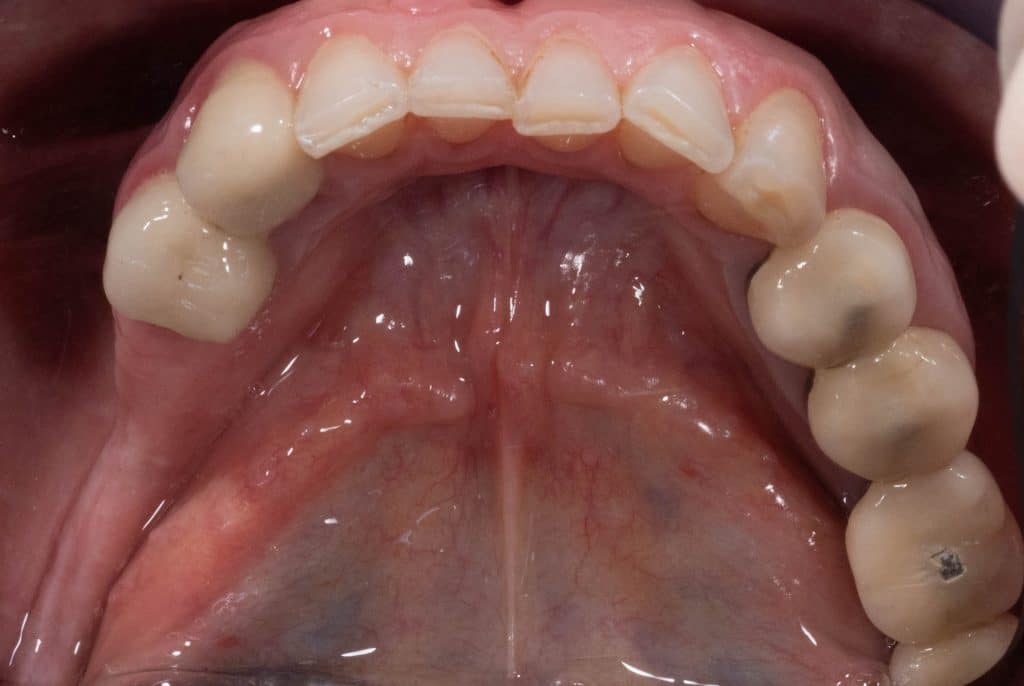

Initial clinical situation- Occlusal view

Clinical situation 2 months after second surgery- Occlusal view

Final prosthetic rehabilitation- Occlusal view